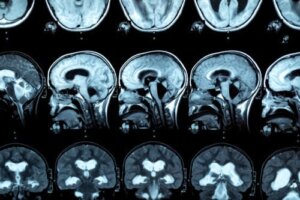

يمكن أيضًا تقدير ارتخاء الجسم الثفني إذا تم عمل صورة دماغية. في بعض الحالات ، تظهر علامات متلازمة الانفصال بين الكرة الأرضية.

لتشخيص هذا المرض ، يتم إجراء التصوير بالرنين المغناطيسي ، بحيث يتم ملاحظة الآفات في الجسم الثفني. في هذا الصدد ، تشير الأبحاث إلى أن الأشخاص الذين يعانون من اضطراب تعاطي الكحول يظهرون انخفاضًا في سماكة الجسم الثفني الأمامي والوسطى والخلفي ، بالإضافة إلى اختلافات في حجم الفص الجبهي والتلم القشري.